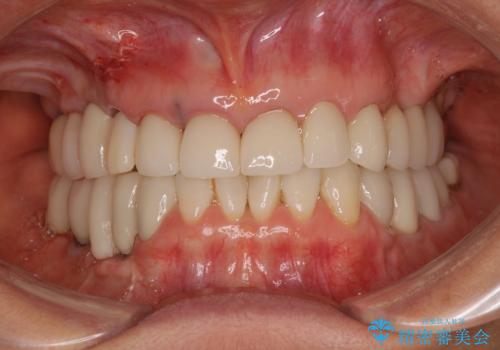

全顎的な治療後に、急遽ニューヨークへ転居されることとなったのですが、治療後から経過観察を行っていた右上犬歯が歯肉縁下に及ぶむし歯のため、クラウンが土台ごと外れてしまったとの連絡がありました。

他の部位にインプラント治療を行っていたことから、こちらの歯に対してもインプラントによる補綴治療を希望されたため、1泊での帰国時に抜歯、インプラント埋入、仮歯の装着を行い、数ヶ月後の帰国時にオールセラミッククラウンの型取りと装着を行う計画としました。

インプラント埋入時は1泊、補綴治療時には3週間ほど日本に滞在していただき、2回の渡航で無事に治療を終えることができました。